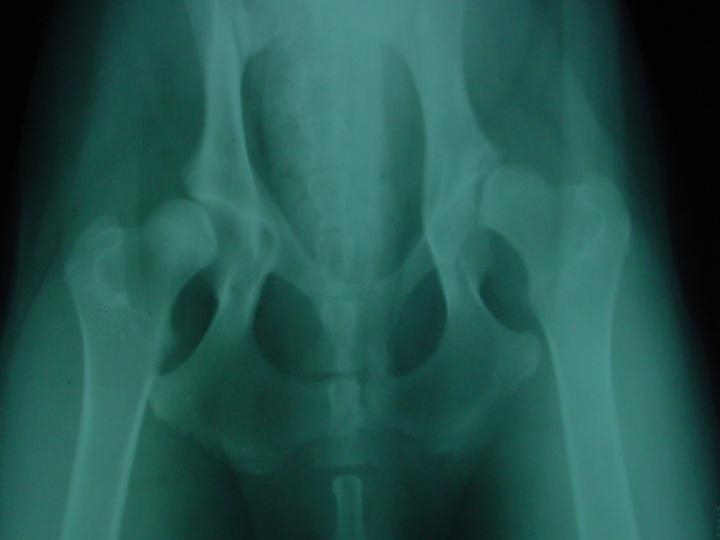

Rx: Em primeiro lugar fizemos uma sedação profunda do paciente sem a qual é impossÃvel obter um Rx com as caracterÃsticas exigidas para fazer um estudo exaustivo da displasia.

Após a sedação o paciente é colocado na mesa numa posição simétrica e paralela. No enquadramento do chasis temos que ter as asas do ilium, os buracos obturadores, ambas as rótulas no centro das trócleas e os fémures paralelos. Obtido o Rx fizemos a medição dos ∢s. O ∢ de Norberg-Obsson < 90º.